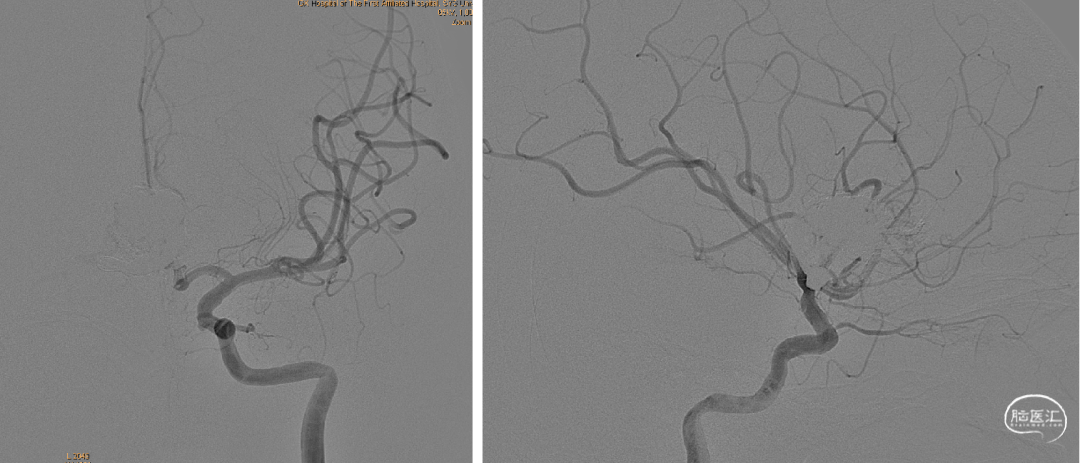

经静脉入路超选到位

经Echlon10微导管填入弹簧圈做塞子

经Apllo微导管注入Onyx胶

术后造影脑动静脉畸形消失